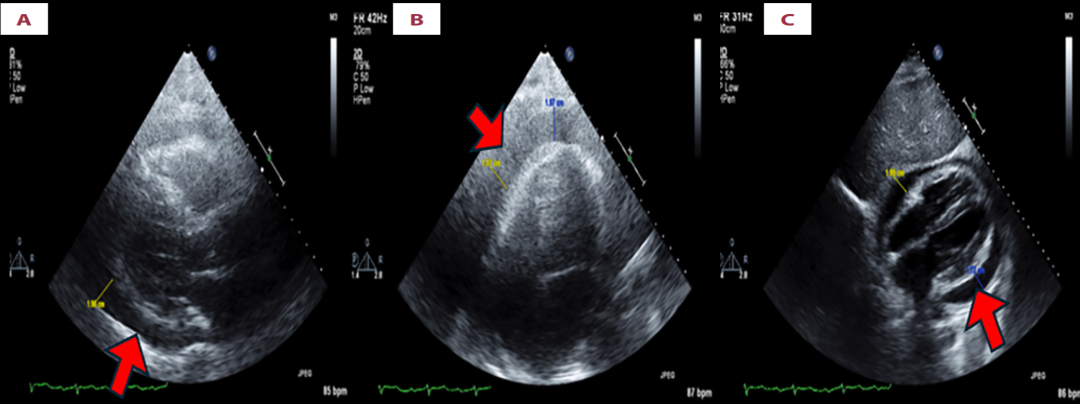

便携式胸部X光片提示可疑充血性心力衰竭,心电图显示为心房颤动。经胸超声心动图显示中量心包积液,无心脏压塞迹象。

Transthoracic echocardiogram shows a moderate-to-large circumferential pericardial effusion measuring approximately 1.87 cm in diastole (blue caliper) and 1.87 cm posteriorly (yellow caliper). The effusion appears echo-dense with heterogeneous internal echoes, consistent with hemorrhagic or complex fluid rather than a simple serous effusion, as illustrated in the parasternal long-axis view (A), apical four-chamber view (B), and subcostal view (C), with the effusion highlighted by red arrows in each image.